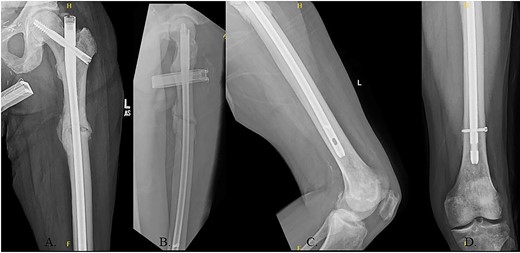

The hip was extended, and a ball-tipped guidewire was successfully passed across the fracture site to a center–center positionwithin the canal at the level of the knee (Fig. 4C and D). Sequential 0.5-mm reaming from 9 to 13 mm prepared for an 11 × 400 mm, 125° Gamma3® intertrochanteric rod (Stryker© Kalamazoo, MI), with a 95-mm cephalomedullary screw and ×2 distal lateral to medial interlocking 5.0-mm screws (Fig. 5A–D). Through the course of the procedure, 400 cc of blood loss necessitated two units of packed red blood cells.

(A) AP radiograph of left hip with implant; (B) lateral radiograph of left hip with implant; (C) reduced fracture site with implant; (D) distal femur with implant.